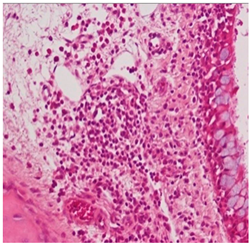

![]() | Grade 2: Moderate lymphoplasmacytic infiltration in the lamina propria with the lymphocytic infiltration of the epithelium lining, resulting in some disorganization and disruption of the epithelium and loss of cilia. |

![]() | Grade 3: Severe lymphoplasmacytic infiltration of the edematous lamina propria. The respiratory epithelium is disrupted and sometimes ulcerated (top right of image), with marked epithelial lymphocytic infiltration and goblet cell hyperplasia. |